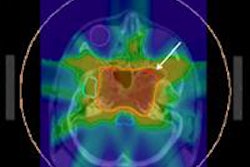

The state-of-the-art center boasts four treatment rooms, three gantries using isocentric rotational frames, and one fixed-beam room that offers advanced options for patient positioning and irradiation technologies that include IBA's pencil-beam scanning (PBS) technology.